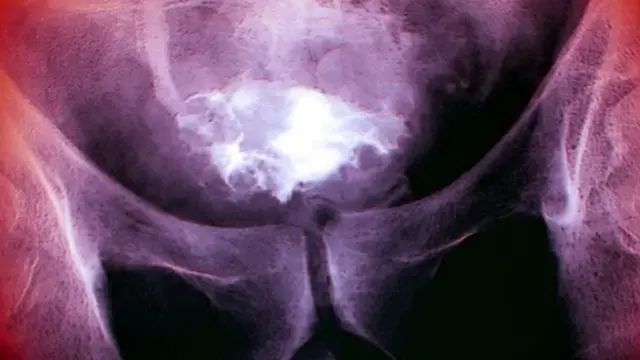

Автор фото, SCIENCE PHOTO LIBRARY